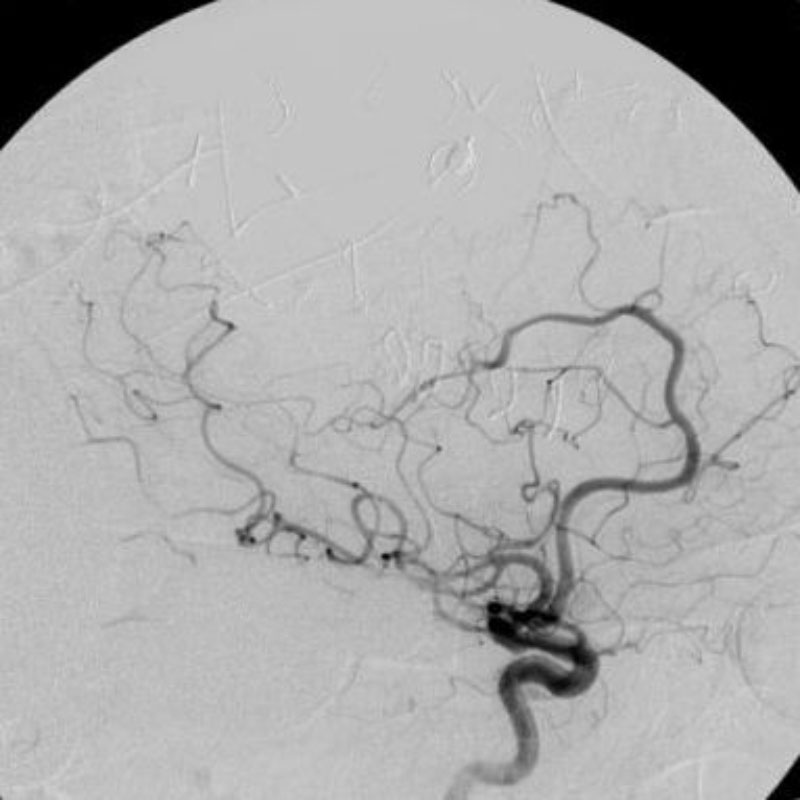

脳血管撮影

手術前

手術後